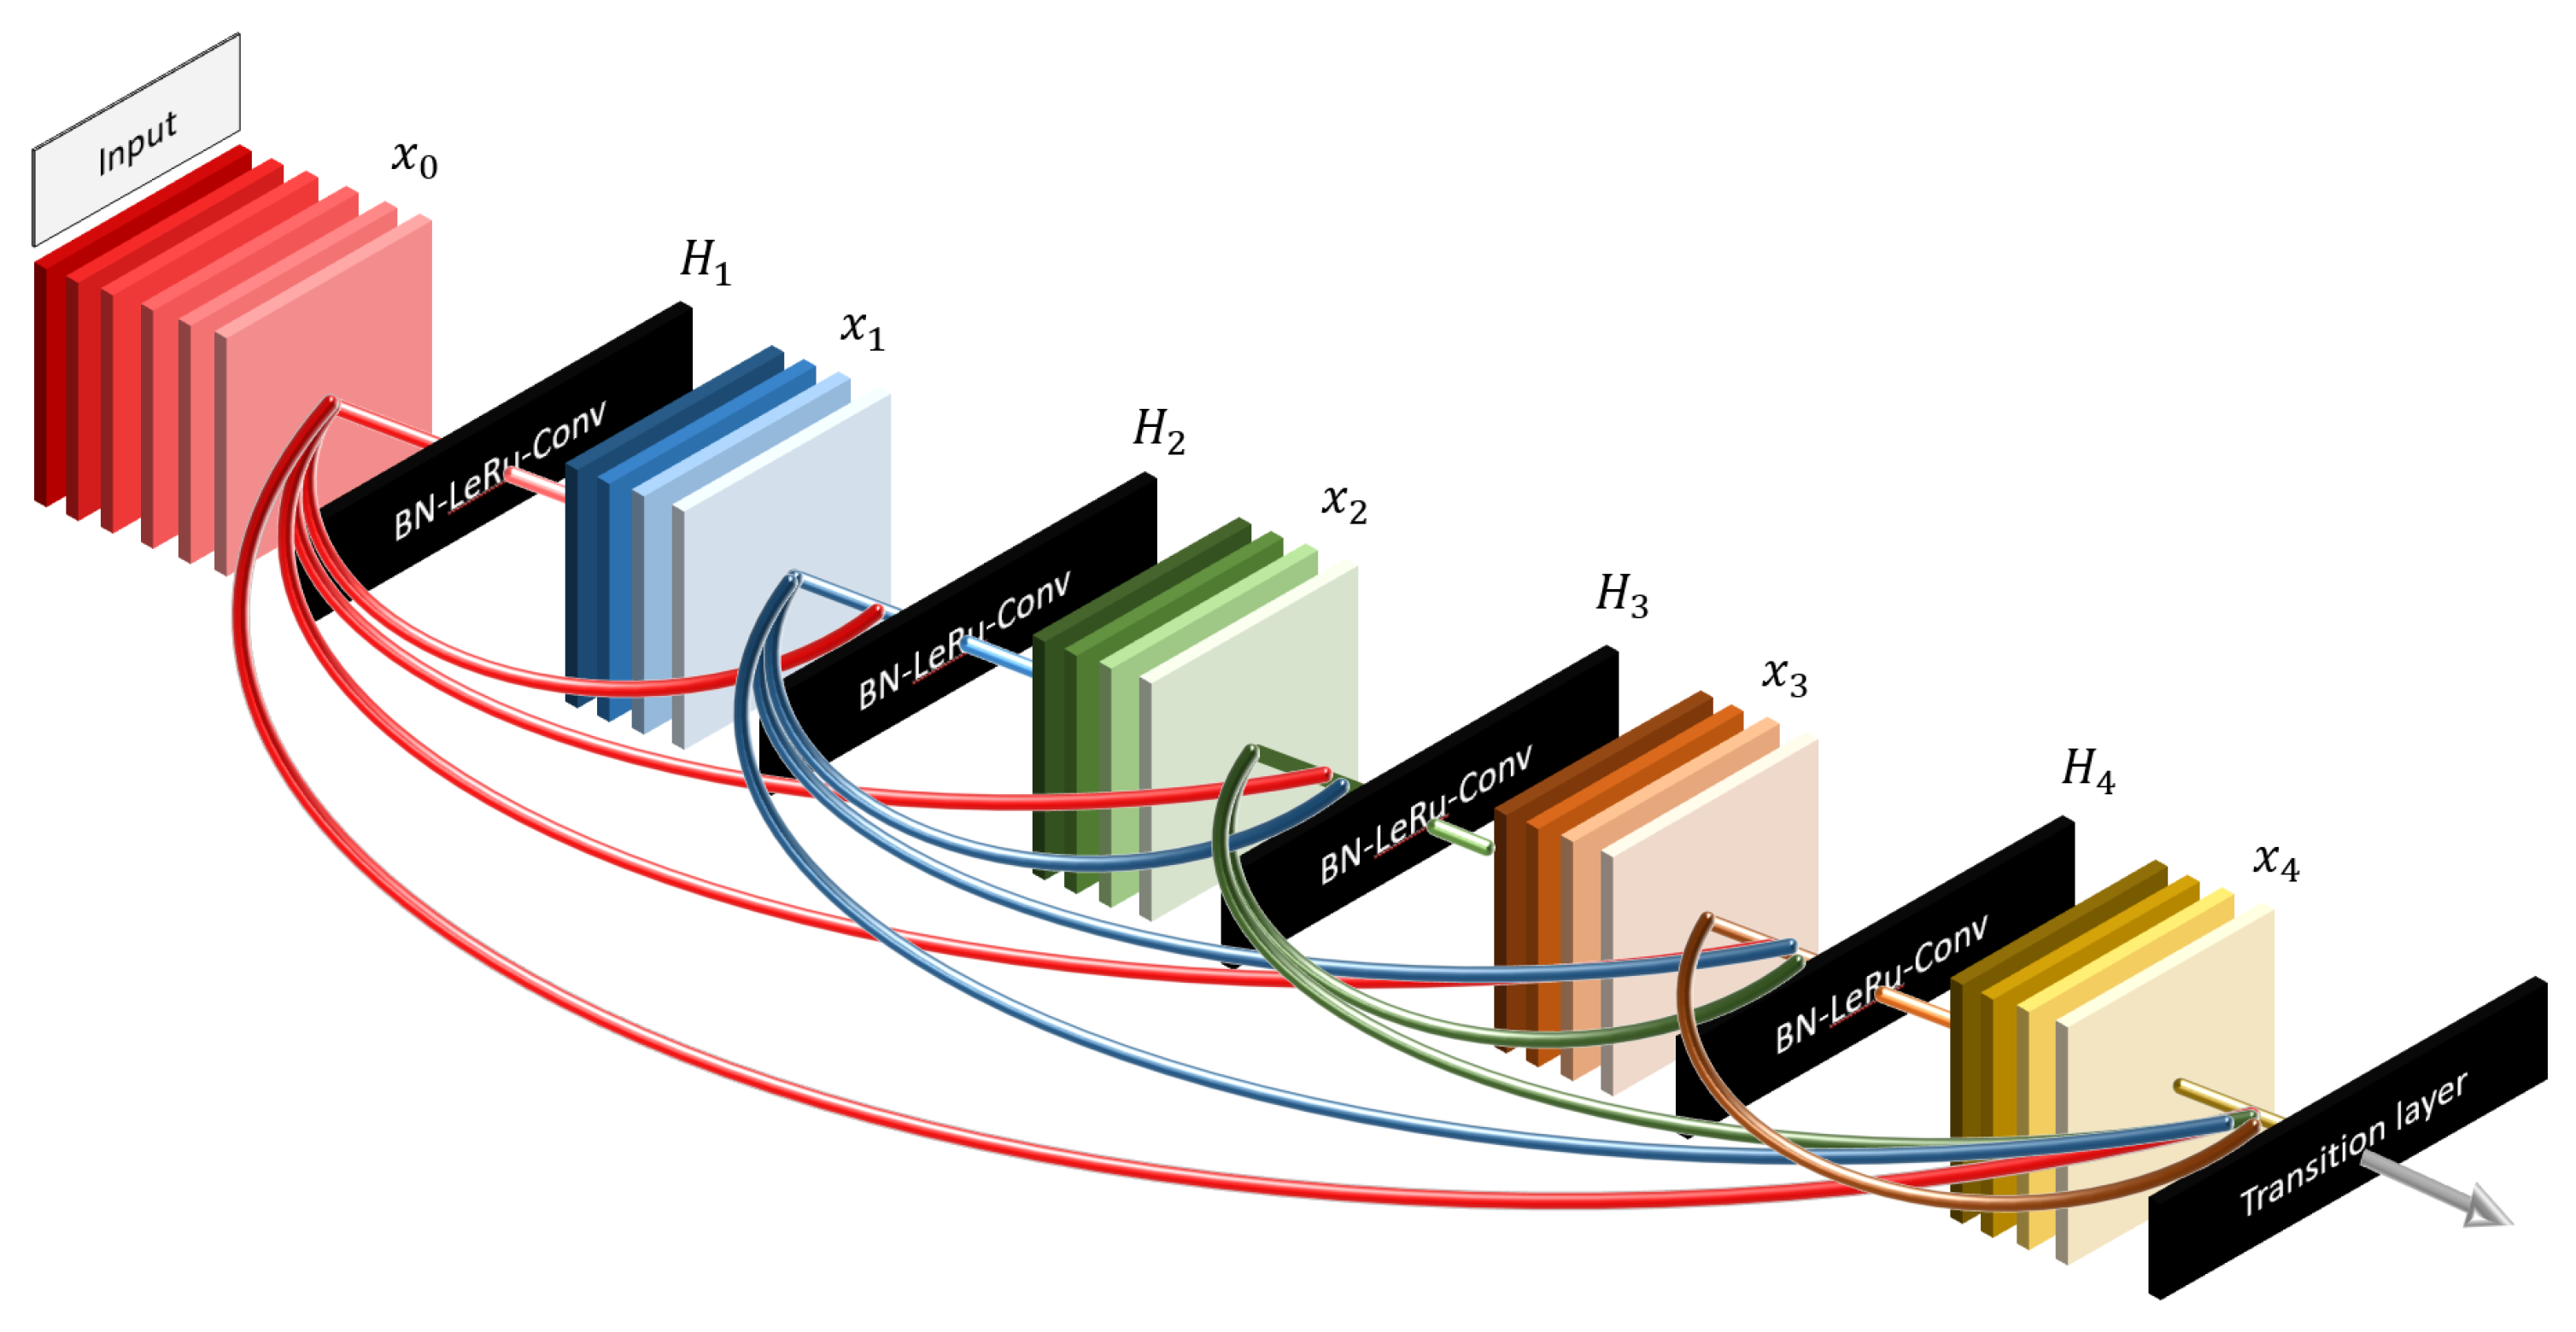

DenseNet201, on the other hand, takes the bypass concept further by connecting each layer to every subsequent layer in a feed-forward manner, as shown in

Figure 4. This dense connectivity approach enables the model to focus on every detail from the beginning, allowing for efficient feature reuse and improving gradient flow.

3. Distinct Focus: We believe that the contrasting focus of ResNet50 and DenseNet201 can provide complementary insights. While DenseNet201 emphasizes the details from the start, ResNet50 is more attuned to the latest layers. These differences may lead to varied results, enriching our understanding of thyroid nodule classification. These well-known and effective models, along with their respective bypass strategies, offer promising capabilities for our specific task, justifying their selection for this study.

Figure 4.

DenseNet structure. DenseNet promotes dense connectivity between layers, allowing for efficient feature reuse and improved gradient flow, ultimately enhancing model performance. Adapted from Huang et al. [

20].

Figure 4.

DenseNet structure. DenseNet promotes dense connectivity between layers, allowing for efficient feature reuse and improved gradient flow, ultimately enhancing model performance. Adapted from Huang et al. [

20].